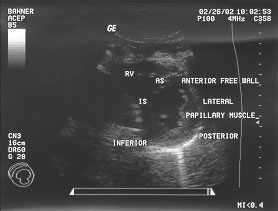

Cardiac - parasternal short axis - mid (labeled)